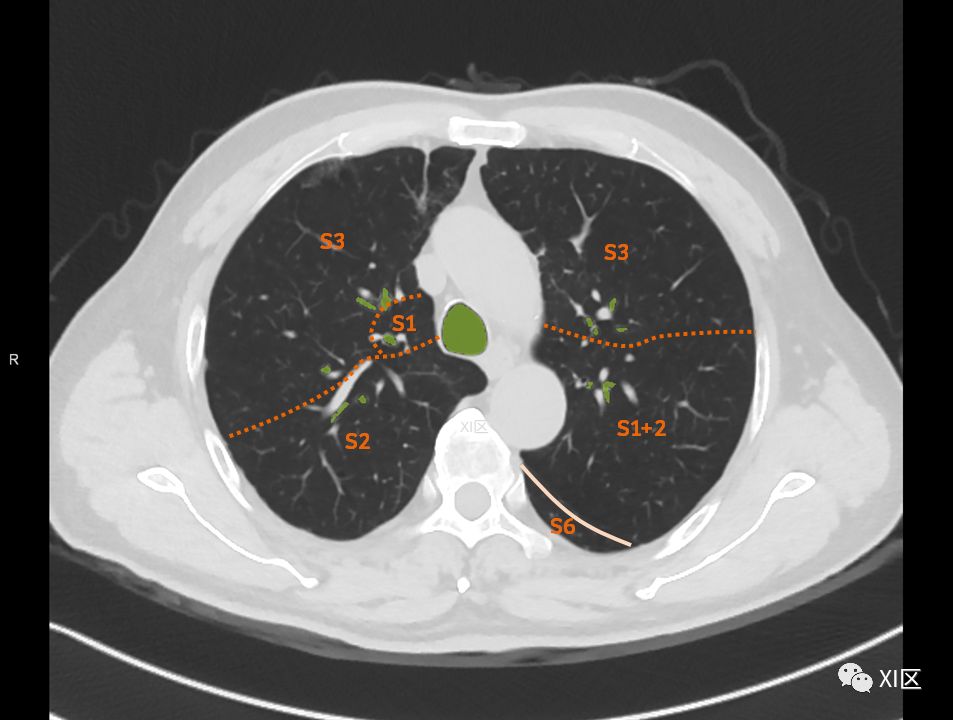

在进行肺的分段时,可以上下观察浏览,沿着相应气管的走形可以更容易准确地进行分段。

肺的分段

肺的断层分段示意图